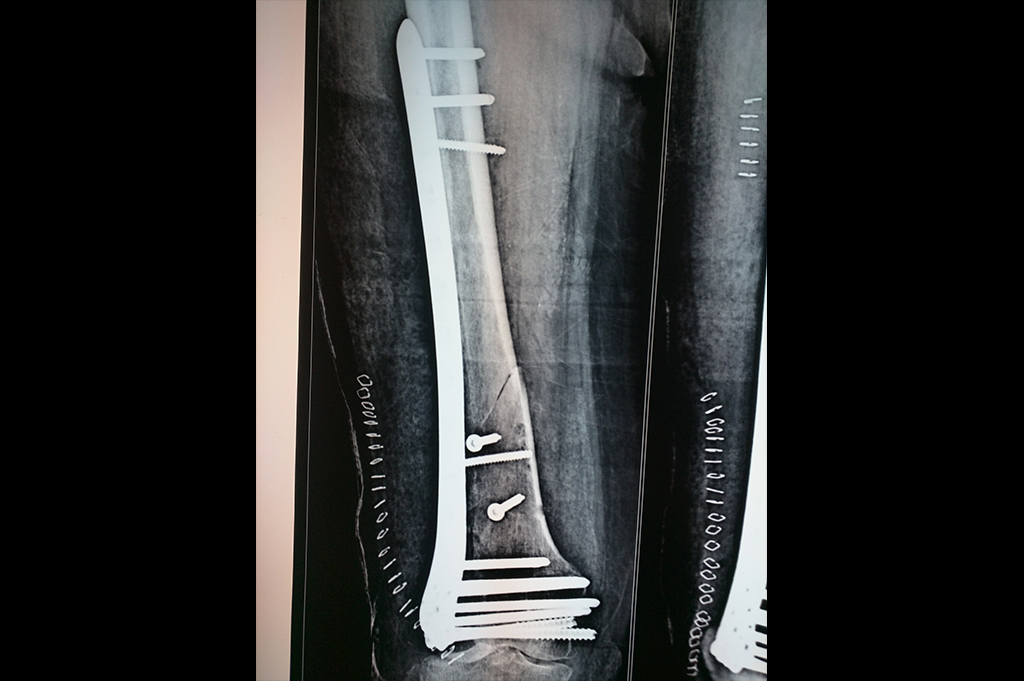

Subtrochanteric Fracture